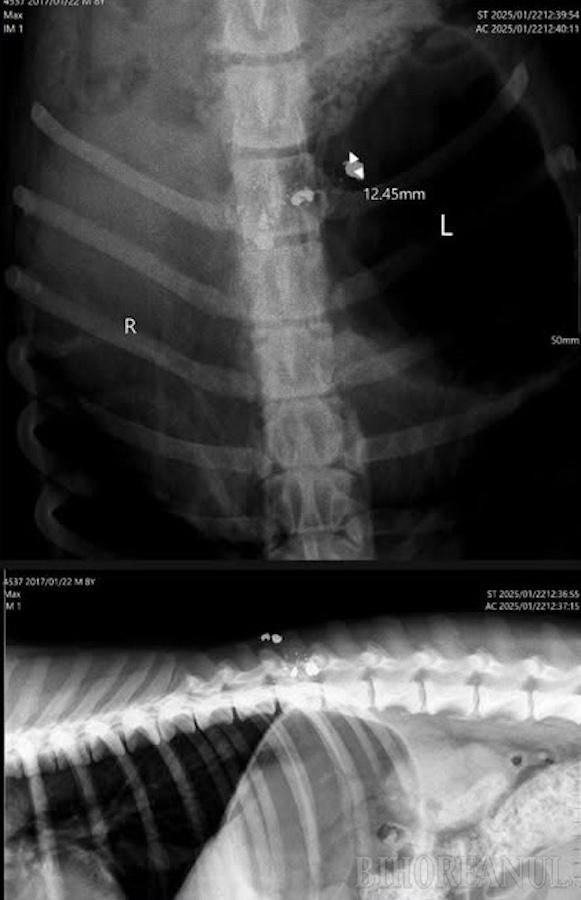

A férfi először egy szalontai állatorvoshoz, majd egy élesdi állatklinikára vitte kutyáját, ahol alapos vizsgálatoknak vetették alá. Megtudta, hogy az eb gerincsérülést szenvedett, amit egy vadászfegyverrel leadott lövés okozott. Az orvos mindent megtett, amit tudott, de nem tudta megmenteni. Egy hét után el kellett altatni. Még mindig nem tértem magamhoz, ez a kutya családtagnak számított – mesélte a férfi. „Ha kárt okozott valakinek a kutya, csak szólnia kellett volna. Kifizettem volna a kárt. Ha bárkit is zavart, csak el kellett volna kergetnie. De megölték, és ezt felháborítónak tartom. Arról nem is beszélve, hogy ez a városban történt, ahol tilos fegyvert használni” – tette hozzá a panaszos.